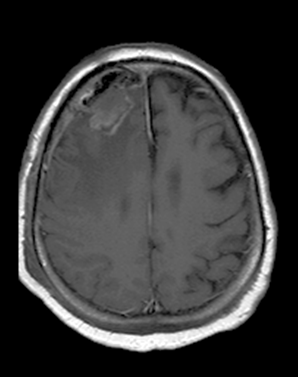

MRI provides even more definitive proof. On T1 weighed images they are usually hypointense, on T2 weighed images their signal is strong. Although these signs are very characteristic, normally they are still insufficient for exact differential diagnostic criteria.

MRI has the greatest sensitivity in the detection of neoplastic brain lesions. The relaxation time of tumor is usually longer than that of the surrounding normal tissues. Therefore on T1W images neoplasms have slightly weaker signal intensity, while on T2W images they are more hyperintense than normal parenchyma. This signal pattern can be very characteristic and has great diagnostic value. However, secondary neoplastic signs, such as mass-effect of the tumor cannot be neglect either. A space occupying lesion can cause:

MRI: Meningiomas show a good Gadolinium enhancement with a characteristic “dural tail” sign (a thickening in the neighboring dura).